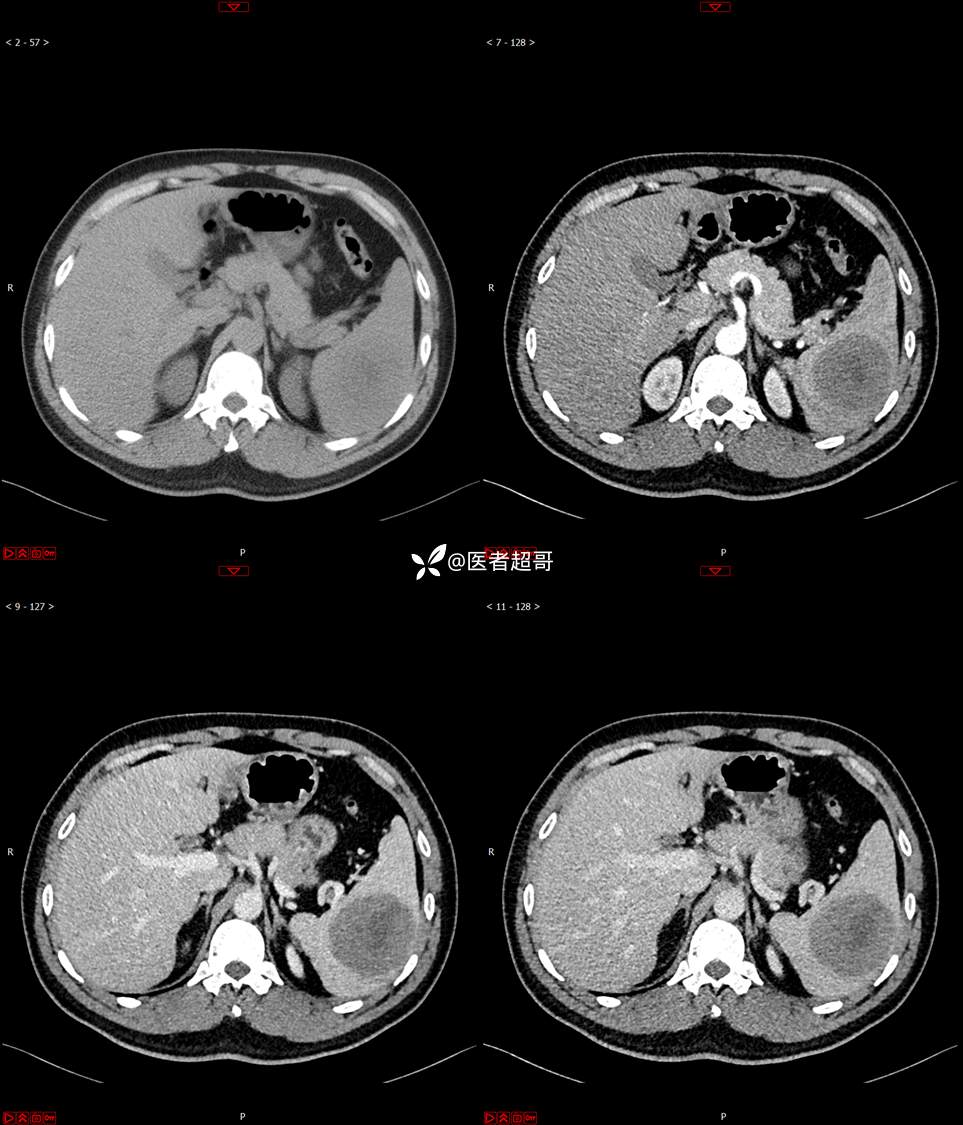

【影诊笔记738】脾脏低密度影,请诊断分析~~

男,33岁 0201215 01

主 诉:发现脾占位2月余。

现病史:患者2月余前体检行肝胆胰脾肾彩超提示脾占位性病变,未予特殊诊治,1天前于区人民医院行肝胆胰脾MR平扫提示脾脏占位性病变,左肾小囊肿,现患者无腹胀、腹泻,无恶心呕吐,无胸闷憋气等症状,今为求进一步治疗,患者来我院就诊,门诊以“脾占位性病变”收入院。患者自发病以来,一般情况可,神志清,精神可,饮食、二便正常,睡眠可,体重体力无明显改变。